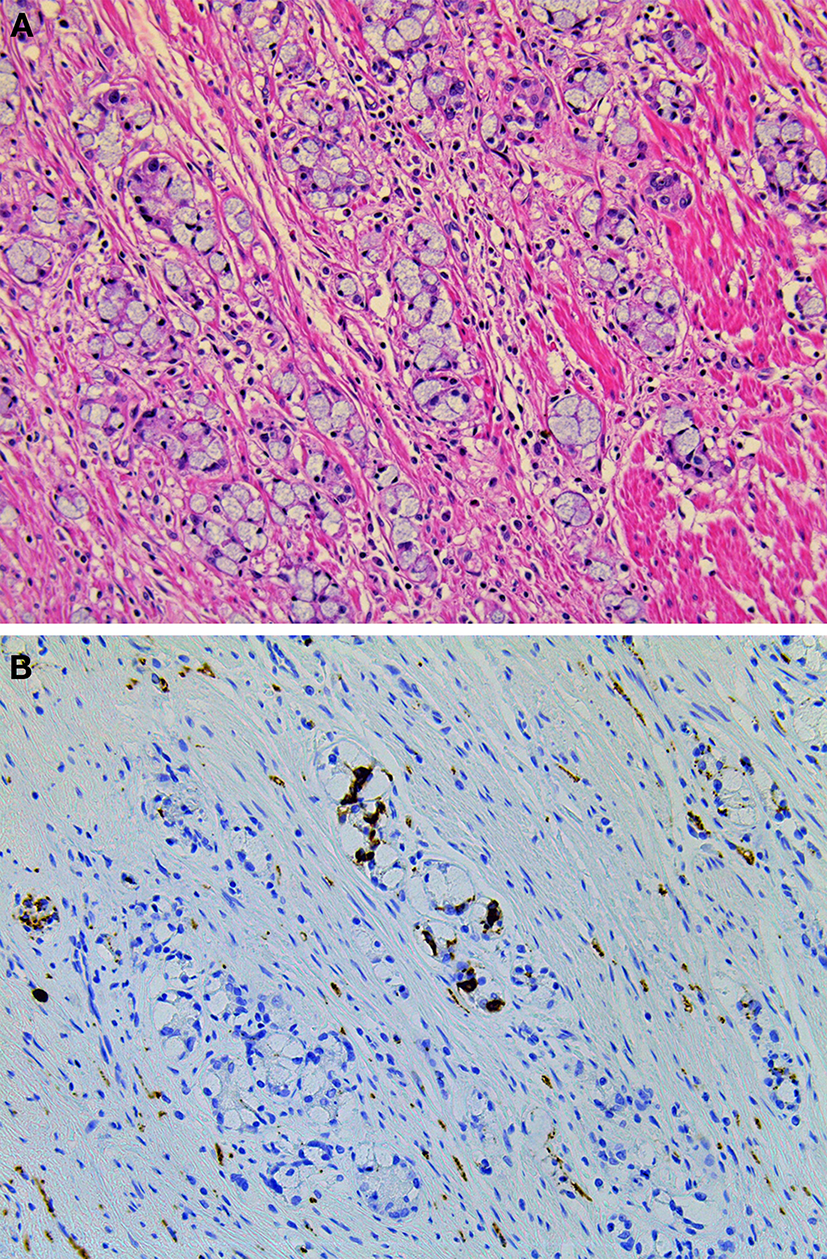

Type-1 and Type-2 NETs are associated with enterochromaffin-like-cell (ECL-cell) hyperplasia and hypergastrinemia. In contrast, Type-3 NETs are not associated with these conditions (Scherubl et al., 2010). Type-1, 2, and most Type-3 NETs are considered to originate from histamine-producing ECL-cells which immunohistochemically express vesicular monoamine transporter 2 (Rindi et al., 2000a; Kloppel et al., 2004, 2007; Scherubl et al., 2010). Histologically, Type-1 and Type-2 NETs show a trabecular or nodular pattern (Figures 5A–D). The Ki-67 index is usually less than 2% (Scherubl et al., 2010). Most Type-3 NETs are more aggressive than Type-1 and Type-2 NETs; they are arranged in a solid, trabecular pattern and occasionally have a high proliferation rate (Kloppel et al., 2007; Scherubl et al., 2010). Type-3 NETs often invade deeply, display lymphatic and vascular invasion, and are associated with local and/or distant metastases (Rindi et al., 1999).

Figure 5

Type-1 neuroendocrine neoplasm (NEN) of the stomach. Tumor cells proliferate in a trabecular fashion in the submucosa. Enterochromaffin-like-cell (ECL-cell) hyperplasia is scattered in the mucosa (H and E stain, A: low power view, B: high power view). Synaptophysin is positive for tumor and ECL-cell hyperplasia (C: low power view, D: high power view).